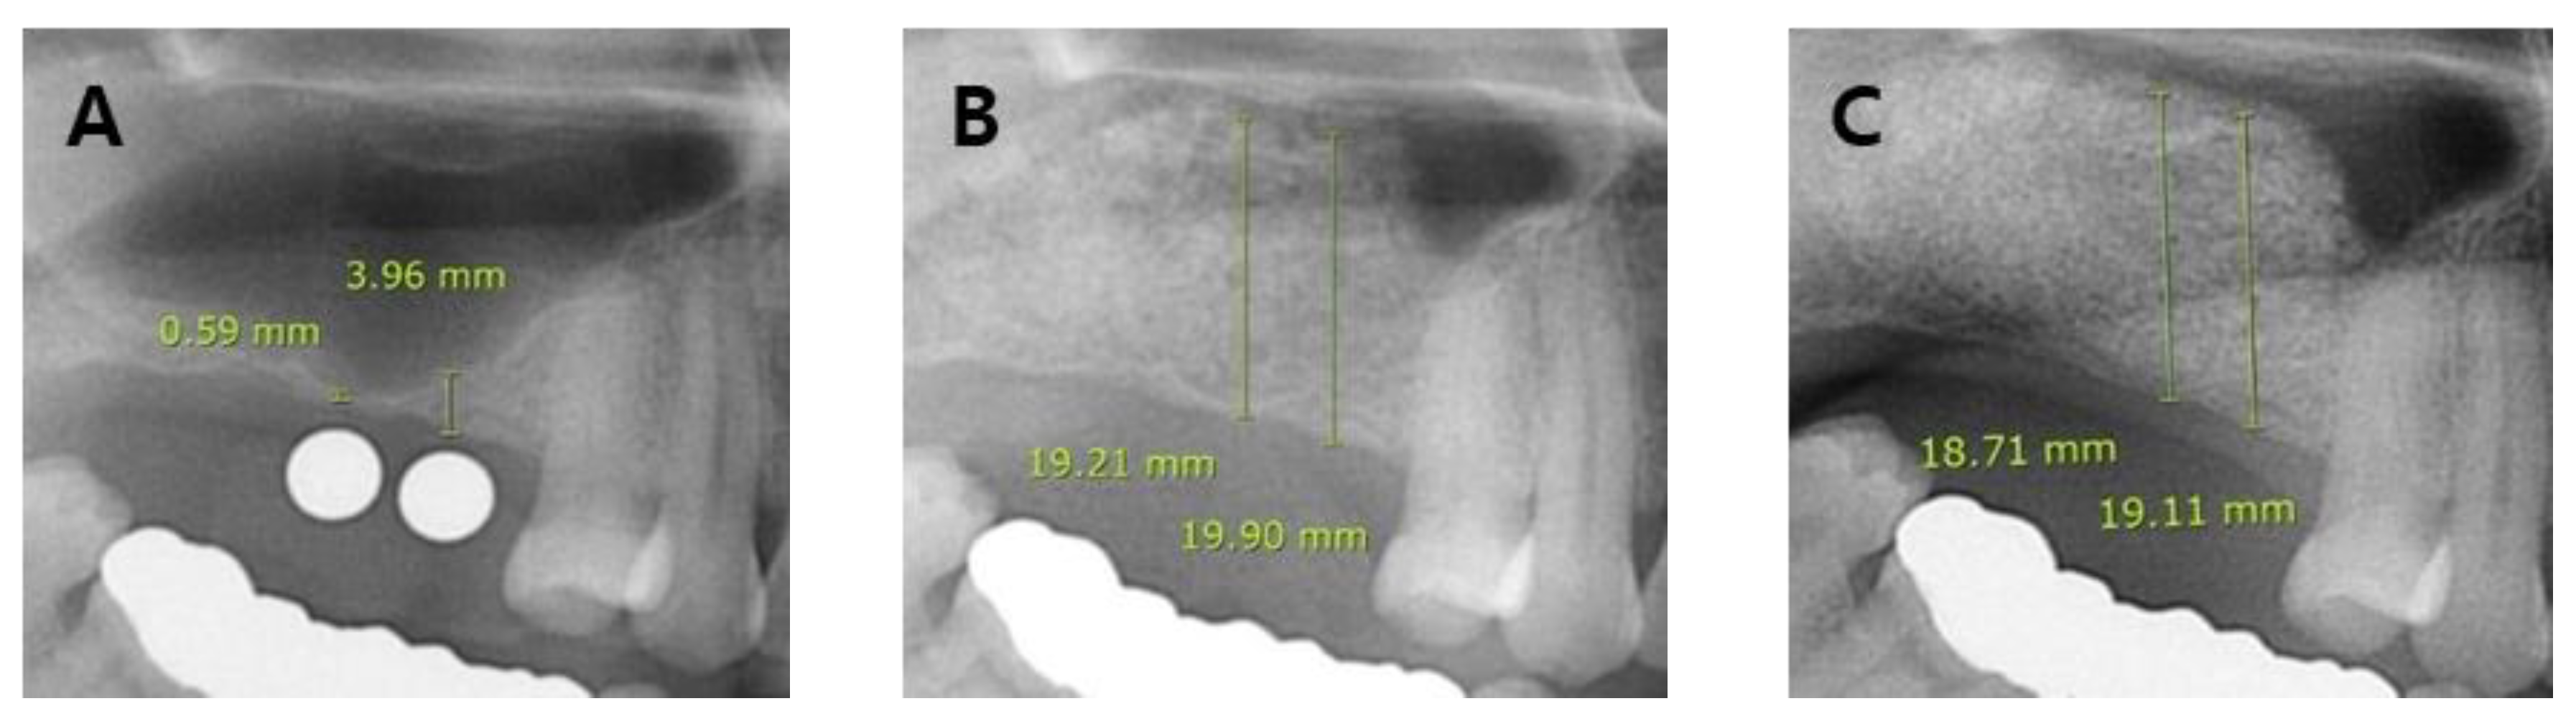

- (A)

- Group 1: No SMP but the membrane was weakened (or thinned) during sinus lift procedure;

- (B)

- Group 2: SMP was small to medium in size (< 10 mm) during sinus lift procedure;

- (C)

- Group 3: SMP was large in size (> 10 mm) during sinus lift procedure;

| Residual Bone Height | <4.0 | 13 (86.7) | 2.037 ± 1.436 | 10 (90.9) | 2.036 ± 1.415 | 10 (83.3) | 2.200 ± 1.351 | 29 (78.4) | 2.270 ± 1.441 |